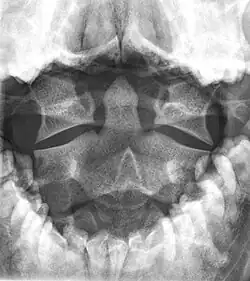

Axis im Röntgenbild durch den geöffneten Mund. Man erkennt gut den Dens axis.

Der Axis unterscheidet sich durch seine Form von allen anderen Wirbeln. Der Wirbelkörper ist relativ groß und massiv. Hervorstechendes Merkmal ist der Dorn oder Zahn des Axis (Dens axis) auf der Oberseite vorne (Mensch) beziehungsweise Vorderseite (vierfüßige Säugetiere) des Wirbelkörpers. Er stellt ontogenetisch den Wirbelkörper des Atlas dar und liegt genau dort, wo diesem fast ringförmigen Wirbel der Körper fehlt. Der Dens geht von der Oberseite des Wirbelkörpers gerade nach oben, besitzt auf seiner Vorder- und Rückseite eine Gelenkfläche und endet mit einer abgerundeten Spitze.[1]